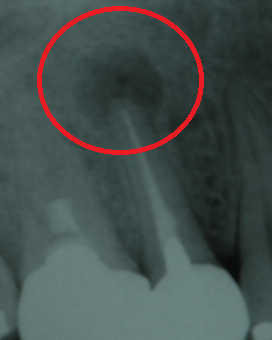

更に、当院では根管治療の精度をさらに高めるために、「CT」も利用しています。CTは一般的な2次元レントゲンと比較し立体的で詳細な画像を撮影できるため、治療必要箇所を見落とすことなく、より高い成功率を実現できます。

上記の画像は、「左」が3次元のCT画像で、「右」が2次元レントゲン画像です。左の赤丸がついている「黒い部分」が問題の箇所ですが、右の画像では黒く映っていません。CTであれば、はっきり確認できるため、治療すべき部位を見落とすリスクが下がります。